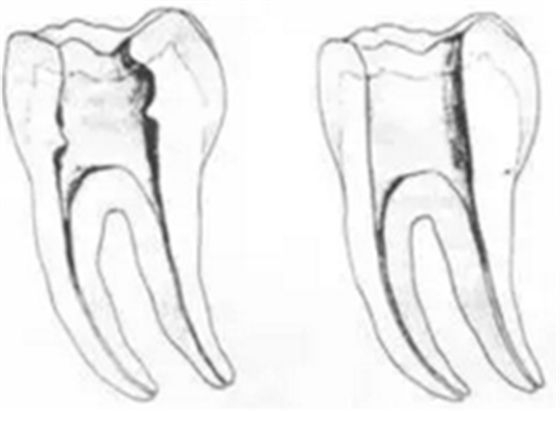

三、開髓孔

1. 正常開髓孔的位置和大小

左圖為正常開髓孔的大小和位置。左邊圖為下顎,右邊圖為上顎。

2. 根管治療中開髓孔的設(shè)計標(biāo)準(zhǔn)

根管治療需去除髓腔內(nèi)容物(去除髓室頂),建立所有根管的入路,允許沖洗液大量沖洗。開髓孔的設(shè)計標(biāo)準(zhǔn)以建立通路為目的,從而建立良好的視野和術(shù)野。

( 1 )直線通路:根管治療時需要一個直線通路,直線通路能夠達(dá)到根尖三分之一

測量標(biāo)準(zhǔn):以允許根管器械直線并直接進(jìn)入根尖 1/3 且不接觸冠方各壁為標(biāo)準(zhǔn)。

( 2 )髓腔其他改變:如髓室頂、繼發(fā)性牙本質(zhì)、修復(fù)性或增齡性牙本質(zhì)。見左圖。

右圖中有繼發(fā)性牙本質(zhì),切削后獲得直線通路。